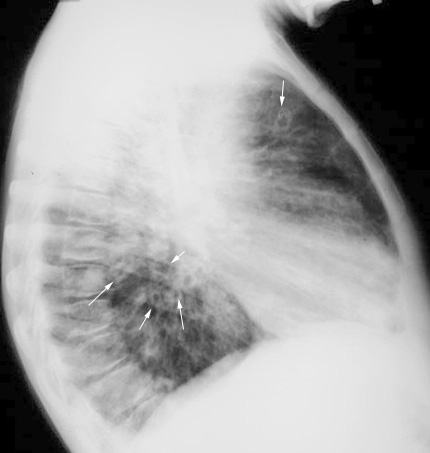

What are the contents of a cavity?